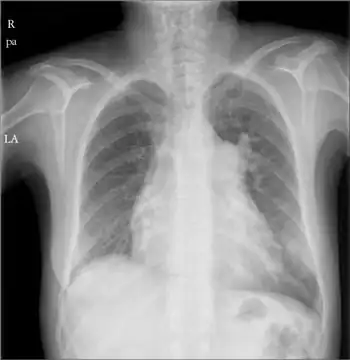

Right atrial enlargement

Right atrial enlargement (RAE) is a form of cardiomegaly, or heart enlargement. It can broadly be classified as either right atrial hypertrophy (RAH), overgrowth, or dilation, like an expanding balloon. Common causes include pulmonary hypertension, which can be the primary defect leading to RAE, or pulmonary hypertension secondary to tricuspid stenosis; pulmonary stenosis or Tetralogy of Fallot i.e. congenital diseases; chronic lung disease, such as cor pulmonale. Other recognised causes are: right ventricular failure, tricuspid regurgitation, and atrial septal defect.[1]

It is characterized by a high P wave amplitude (P pulmonale), i.e. a height greater than 2.5 mm in inferior ECG leads (II, III, aVF); and greater than 1.5 mm in right sided precordial leads (V1, V2). [2]